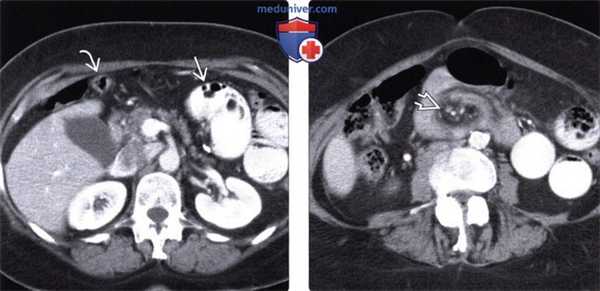

(Слева) На аксиальной КТ с контрастным усилением определяется овоидной формы группа петель тощей кишки в верхнем левом квадранте. Обратите внимание на четко очерченные края грыжевого мешка вокруг выпавшей кишки, а также на брыжеечные сосуды, сходящиеся к центру мешка. Данные изменения типичны для левосторонней пара-дуоденальной грыжи.

(Справа) На отсроченной рентгенограмме верхних отделов ЖКТ у этого же пациента определяется группа плотно прилегающих друг к другу расширенных петель тощей кишки и замедление прохождения контраста в нерасширенные дистальные отделы тонкой кишки.